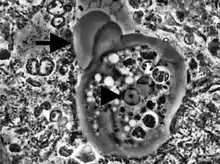

| Entamoeba gingivalis from periodontal pocket [1] | |

It is found in the mouth[5] inside the gingival pocket biofilm near the base of the teeth, and in periodontal pockets.[1] Entamoeba gingivalis is found in 95% of people with gum disease and rarely in people with healthy gums.[6][7] Cyst formation is not present; therefore transmission is direct from one person to another by kissing, or by sharing eating utensils. Only the trophozoites are formed and the size is usually 20 micrometers to 150 micrometers in diameter. Entamoeba gingivalis have pseudopodia that allow them to move quickly and phagocytise the nucleus of polynuclear neutrophils by exonucleophagy in periodontal disease.[8] Their spheroid nucleus is 2 micrometers to 4 micrometers in diameter and contains a small central endosome. There are numerous food vacuoles, which consists mostly of phagocitised PMN nucleus, blood cells, and bacteria. It also causes pyorrhoea.